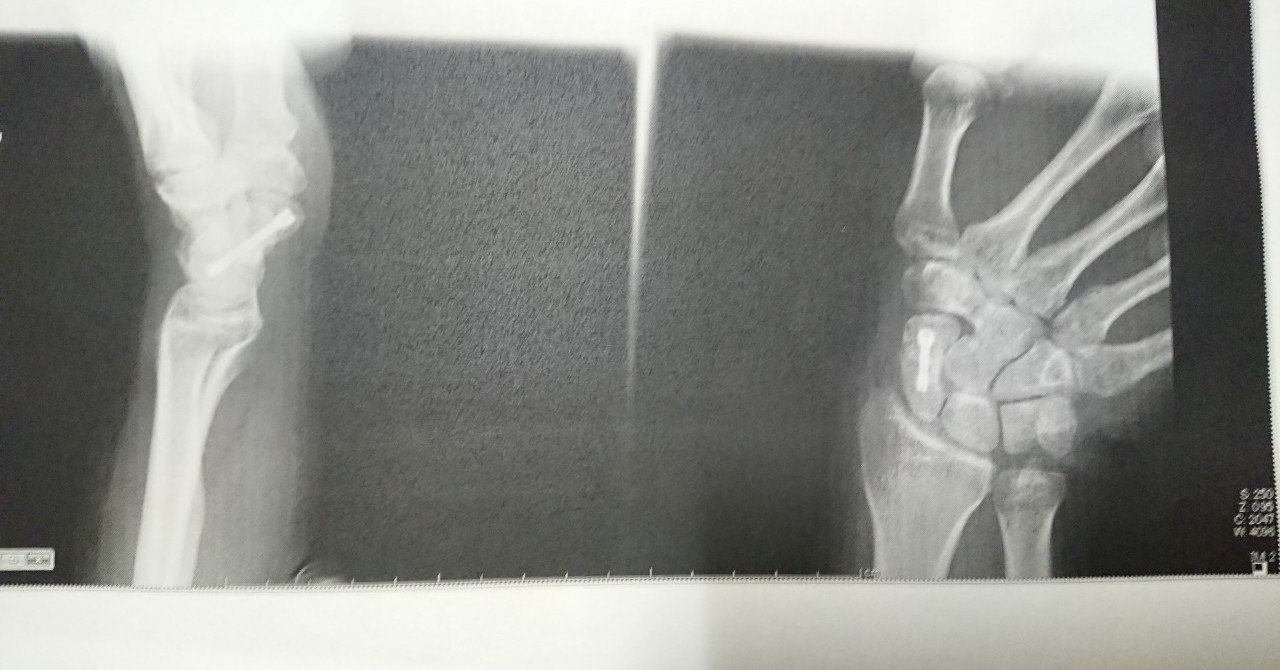

足首 捻挫 骨挫傷-足は踵骨と距骨の二つのセクションに分かれています。 とても面白いと思いませんか? 踵骨グループ →踵(かかと)骨には足の小指(第5趾)と薬指(第4趾)が繋がっている 距骨グループ →距骨には足の母指(第1趾)・人差し指(第2趾)・中指(第3趾)が繋がっている骨挫傷とは? 外傷や関節同士の衝突などにより、骨の骨梁に生じた微細骨折を骨挫傷(bone bruise)と言います。 骨髄の浮腫や出血を伴うことが多く、レントゲンやCTでは描出ができず、MRIでのみ描出が可能です。 ですので、MRI装置の普及により認識されるようになった概念と言えます。

骨挫傷とは? 外傷や関節同士の衝突などにより、骨の骨梁に生じた微細骨折を骨挫傷(bone bruise)と言います。 骨髄の浮腫や出血を伴うことが多く、レントゲンやCTでは描出ができず、MRIでのみ描出が可能です。 ですので、MRI装置の普及により認識されるようになった概念と言えます。骨挫傷とは? 外傷や関節同士の衝突などにより、骨の骨梁に生じた微細骨折を骨挫傷(bone bruise)と言います。 骨髄の浮腫や出血を伴うことが多く、レントゲンやCTでは描出ができず、MRIでのみ描出が可能です。 ですので、MRI装置の普及により認識されるようになった概念と言えます。足首を内側に捻ったような状態になると、 多くは外側の靭帯を傷つけてしまいます。 しかし、同時に、距骨の内側の軟骨を傷めることもあります。 一回の大きな捻挫で受傷する場合もありますし、